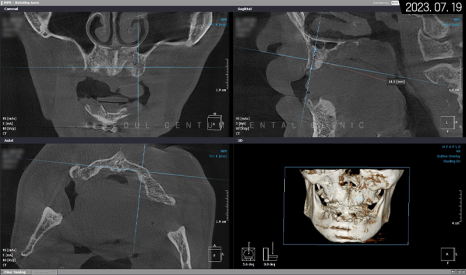

그래서 아래턱을 보존할 수 없는 영구치를 먼저 발치하고 임시 틀니를 사용하면서 저작 기능을 갖기로 했죠. 상악은 픽스처를 고정했고 위턱뼈 어금니 위의 상악동막이 내려왔기 때문에 측방 상악동 거상술도 시행해야 했습니다. 나머지 치조체는 픽스처 고정 위치에 따라 치조정 술식으로 뼈이식재를 넣기로 했습니다.

위턱뼈의 1차 인공 치근 식립을 마치고 나서 3~4개월 후 2차 힐링 어버트먼트를 연결하기로 했으며 동시에 아래턱도 자가골 유도 재생이 어느 정도 진행되었기에 필요시 치조골 이식과 함께 픽스처를 고정해서 1차 수술을 마무리하기로 했습니다.

임플란트 풀케이스는 환자분의 치조체 상태가 중요하며 픽스처 고정도 6~9개까지 골 소실 여부, 개인 필요도 등에 따라 적용할 수 있기에 정확한 검사와 판단이 요구되는 술식입니다. 또한 폰틱 보철물로 수복하기에 위턱과 아래턱의 각도와 교합 상태를 정확히 확인하고 고려해서 폰틱 제작에 들어가야 하는데요. 만일 약간이라도 측정 범위가 어긋나면 저작 기능이 불편해질 수 있으므로 정교하게 설계해서 보철물을 만들어야 합니다.

또, 픽스처가 잇몸뼈 밖으로 돌출되지 않도록 식립해야 하며 어버트먼트도 잇몸에 밀착될 수 있도록 결합해야 하고 폰틱을 수복할 때는 생물학적 폭경까지 고려하면서 진행해야 합니다.